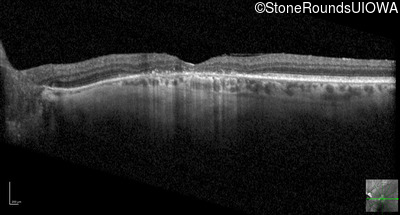

Optical Coherence Tomography - Right - 20/32 -1

Exemplar / OCT Stack

OCT Stack